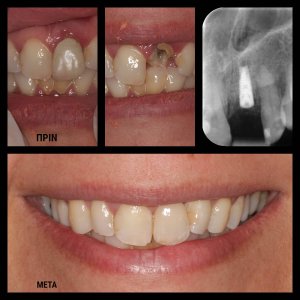

ΠΕΡΙΣΤΑΤΙΚΑ ΜΕ ΤΟΠΟΘΕΤΗΣΗ ΕΝΔΟΟΣΤΙΚΩΝ ΕΜΦΥΤΕΥΜΑΤΩΝ. ΌΠΟΥ ΧΡΕΙΑΣΤΗΚΕ ΠΡΑΓΜΑΤΟΠΟΙΗΘΗΚΕ ΑΝΑΠΛΑΣΗ ΟΣΤΟΥ ΚΑΙ ΟΥΛΙΚΩΝ ΕΛΕΙΜΜΑΤΩΝ ΜΕ ΧΡΗΣΗ ΜΟΣΧΕΥΜΑΤΩΝ ΚΑΙ PRF